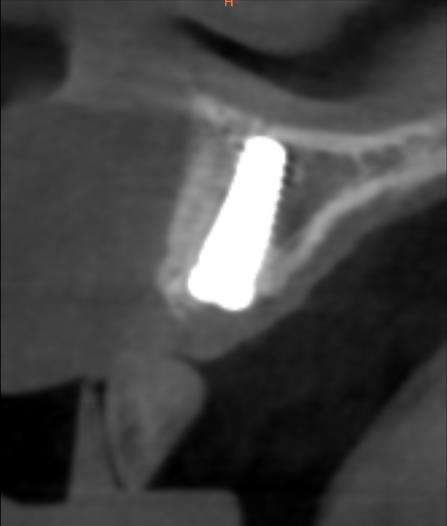

Fig. 2: Bone Graft with 4 mm of New Bone Saved the Implant

We first detoxify the implant surface, then add bone graft material enhanced with growth factors and cover it with a protective membrane to encourage new bone formation (Fig. 2). Four millimeters of bone can often be regenerated to shield the implant (Fig. 2). Throughout, a temporary bridge maintains aesthetics and function by seating over the site (Fig. 3).